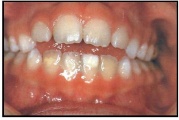

Lutipudelikaariese kahjustused

Lutipudelikaaries